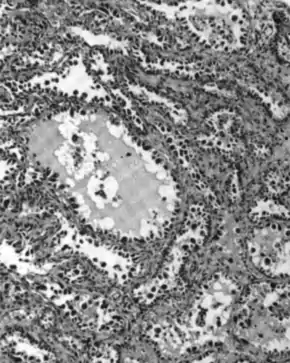

| Micrograph of a mucinous ovarian carcinoma stained by H&E | |

Mucinous adenocarcinomas make up 5–10% of epithelial ovarian cancers. Histologically, they are similar to intestinal or cervical adenocarcinomas and are often actually metastases of appendiceal or colon cancers. Advanced mucinous adenocarcinomas have a poor prognosis, generally worse than serous tumors, and are often resistant to platinum chemotherapy, though they are rare.[29]